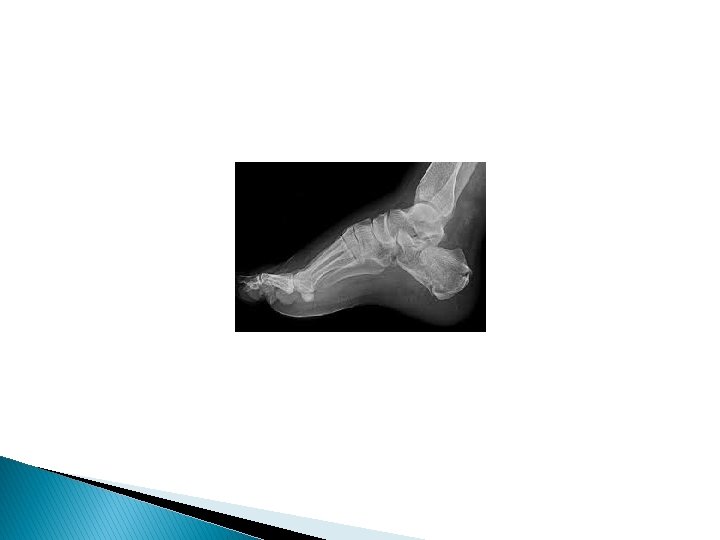

March fracture, also known as fatigue fracture or stress fracture of metatarsal bone, is the fracture of the distal third of one of the metatarsals occurring because of recurrent stress.

Jones fracture is a fracture in the metadiaphyseal junction of the fifth metatarsal of the foot